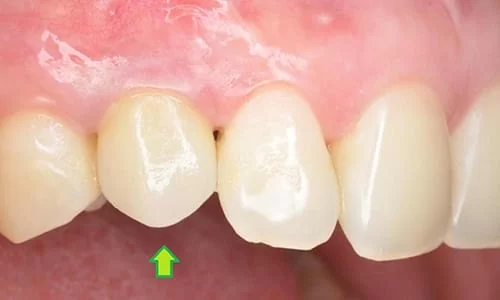

植牙前拔除乳牙後

植牙假牙裝置後